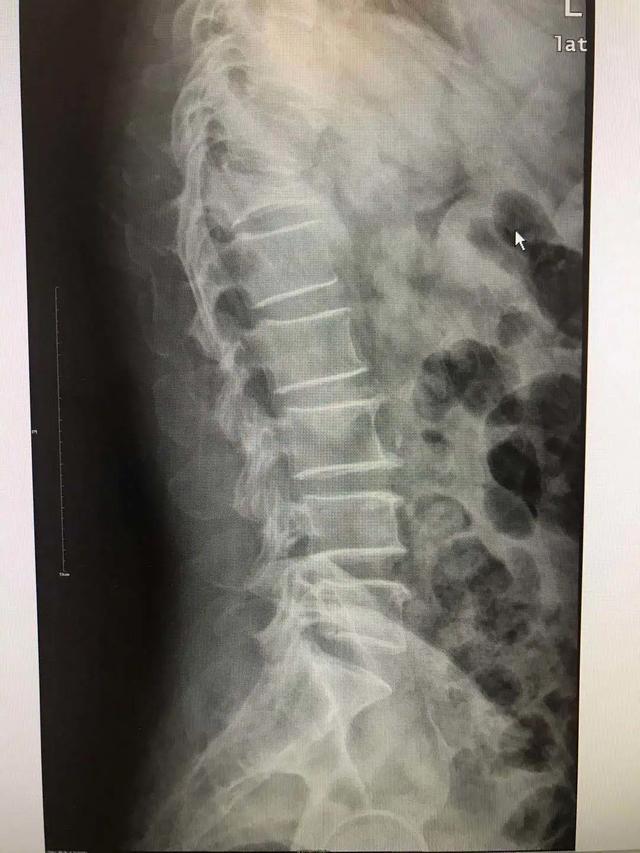

医生检查发现胡奶奶的胸椎、肋骨多处骨折,胸腔还有积液。